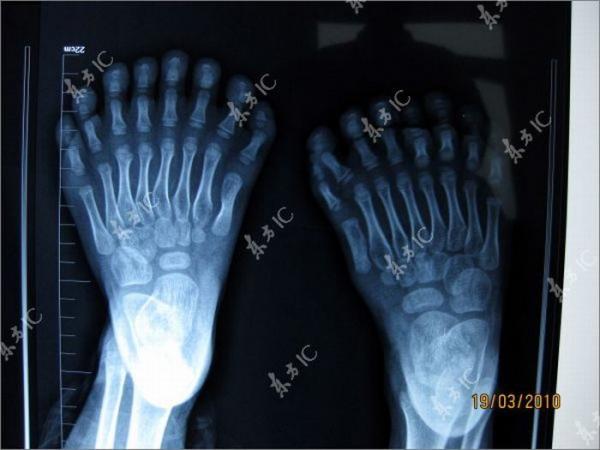

Китайский мальчик с 30-ю пальцами на руках и ногах (13 фото)

У шестилетнего ребенка 15 пальцев на руках и 15 на ногах. На каждой руке мальчика срослись по три пальца. Ребенку поставлен диагноз «полидактилия» (многопалость), который представляет собой генетическую мутацию.